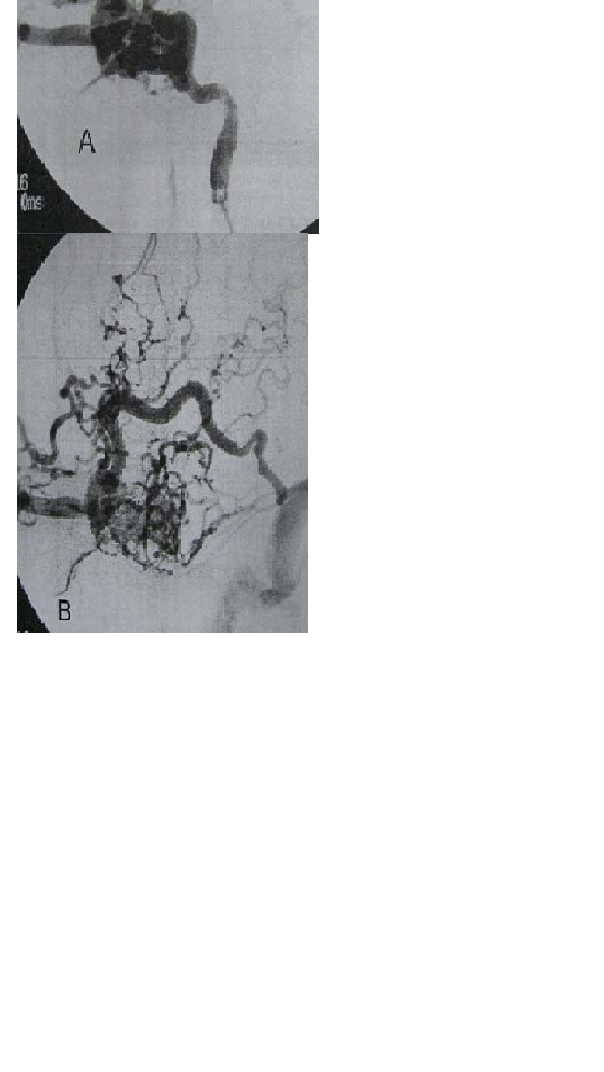

Seorang laki-laki usia 28 tahun mengalami kecelakaan motor. Setelah satu minggu keluar dari perawatan rumah sakit, pasien mengalami demam, sakit kepala retro-orbital parah, diplopia dan proptosis mata kiri, dan segera dibawa ke ruang gawat darurat, CT scan atas otak menunjukkan andanya kontusi frontal 2 x 3 cm kiri yang mengalami retak tulang depan dan sedikit bergeser dan bertahan sejak saat cedera awal. Tingkat sedimentasi eritrosit (ESR) dan protein C-reaktif

(CRP) agak naik. Angiogram pasien tampak pada gmbr di bawah ini :

A. Drainase Vena kortikal retrograde

B. Pengumpan artero meningeal majemuk

C. Pasokan arteri karotid dalam dan luar berganda